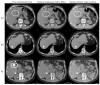

Materials and methods: This Institutional Review Board-approved retrospective study included 98 consecutive patients who had a history of liver cancer and underwent multiphasic liver CT exams with rsDECT applied during the late arterial phase between June 2015 and December 2015. Virtual monochromatic 70 keV, material density images (MDI) iodine (-water) and virtual unenhanced (VUE) images were generated. Radiation dose analysis was performed in a subset of 44 patients who had also undergone a multiphasic SECT examination within 6 months of the rsDECT. Four board-certified abdominal radiologists reviewed 24-25 patients each, and a fifth radiologist re-evaluated all the scans to reach a consensus. The following imaging aspects were assessed by the radiologists: (a) attenuation measurements were made in the liver and spleen in VUE and true unenhanced (TUE) images; (b) subjective evaluation for lesion detection and conspicuity on MDI iodine (-water)/VUE images compared with the virtual monochromatic images/TUE images; and (c) overall image quality using a five-point Likert scale. The radiation dose analyses were evaluated in the subset of 44 patients regarding the following parameters: CTDIvol, dose length product, patient's effective diameter and organ dose using a Monte Carlo-based software, VirtualDose™ (Virtual Phantoms, Inc.) to 21 organs.

Results: On average, image noise on the TUE images was 49% higher within the liver (p < 0.0001) and 48% higher within the spleen (p < 0.0001). CT numbers for the spleen were significantly higher on VUE images (p < 0.0001). Twenty-eight lesions in 24/98 (24.5%) patients were not observed on the VUE images. The conspicuity of vascular anatomy was considered better on MDI iodine (-water) Images 26.5% of patients. Using the Likert scale, the rsDECT image quality was considered to be satisfactory. Considering the subset of 44 patients with recent SECT, the organ dose was, on average, 37.4% less with rsDECT. As the patient's effective diameter decreased, the differences in dose between the rsDECT and SECT increased, with the total average organ dose being less by 65.1% when rsDECT was used.

Conclusion: VUE images in the population had lower image noise than TUE images; however, a few small and hyperdense findings were not characterized on VUE images. Delineation of vascular anatomy was considered better in around a quarter of patients on MDI iodine (-water) images. Finally, radiation dose, particularly organ dose, was found to be lower with rsDECT, especially in smaller patients.